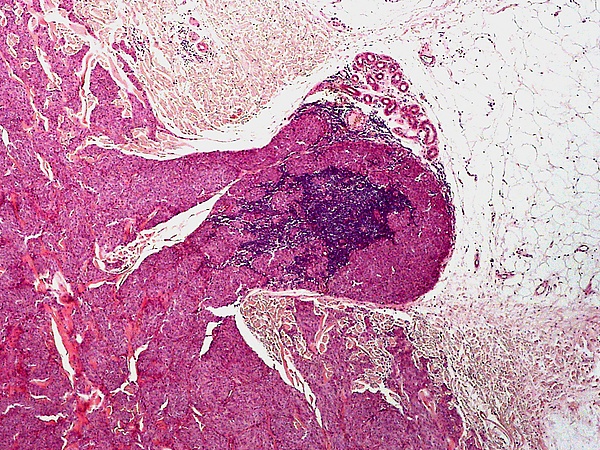

Основным методом подтверждения диагноза голубого невуса является гистологическое исследование биопсийного материала изменённого участка кожи. При простой форме выявляется узловатое скопление слабо пигментированных веретеновидных меланоцитов и выраженных дендритных меланоцитов, расположенных между утолщёнными коллагеновыми волокнами. Часто обнаруживаются меланофаги. Митотическая активность для этой формы нехарактерна[1][5]. Наблюдаются явления склероза в строме[9].

Клеточная форма представлена плотными фестончатыми скоплениями веретеновидных или овоидных меланоцитов, формирующих тяжи и гнёзда, которые могут распространяться в подкожно-жировую клетчатку. Для неё типично более выраженное клеточное строение при отсутствии выраженной цитологической атипии и некроза. Возможны редкие митозы. Часто определяется компонент простой формы внутри клеточного невуса[5].